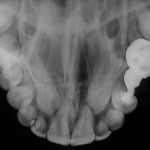

Oclusal

Es un tipo de radiografía intraoral, ya que se realiza desde el interior de la boca. Mediante la radiografía oclusal se pueden ver fracturas del alveolo, los límites de lesiones quísticas o tumorales, dientes incluidos, cuerpos extraños, etc.